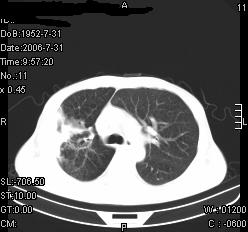

患者,男,54岁,咳嗦,咳痰20天。抗炎治疗2周。现esr76mm/h,目前患者症状明显好转,但发现两次ct片未见明显变化。两次分别做与7.25、7.31。第一次诊断右肺上叶炎症累计胸膜。大家看,从影像上内排除结核吗?

结核的可能性非常大,右上肺病变应该考虑干酪性肺炎。理由:

1.纵隔内多发淋巴结肿大。

2.esr76mm/h。

3.虽经抗炎治疗肺窗病灶有所吸收、减小,但纵隔窗病灶形态、密度、范围无明显变化。如果是单纯的大叶性肺炎,“抗炎治疗2周,目前患者症状明显好转”病灶应该基本消散了,至少也处于吸收消散期,密度变淡、范围变小。同时本病例所示其内的密度不均匀,见多发大小不一空洞样影也不符合大叶性肺炎吸收消散期表现。

病灶特点:片状 索条 结节混杂影,部分融合,密度不均,广泛累及相应胸膜.

临床治疗;二周未吸收.但症状好转.

多考虑:肺结核.